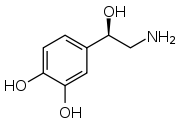

- Dopaminergic (Dopamine and 3-methoxytyramine)

Structure of dopamine

Structure of dopamine- More likely to indicate an extra-adrenal tumor of the head and neck[73]

- Patients are more likely to be asymptomatic; however, they may present with non-specific signs of nausea, vomiting, abdominal pain, diarrhea, and weight loss secondary to the stimulation of dopamine receptors throughout the gastrointestinal tract[62]

- Particularly prevalent in patients with succinate dehydrogenase subunit B genetic variants [62]